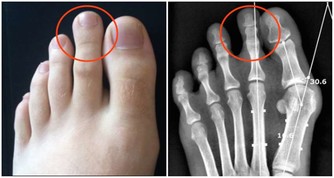

胳膊痛:肺癌的癥狀之一

肺癌的癥狀之一是手臂和胳膊內部有痛感。

如果手臂和胳膊內部的痛感,隨著時間增長變得越來越嚴重,

很可能是因淋巴結腫大壓迫神經導致的,而這是肺癌的癥狀之一。

這種痛感不像肌肉酸痛,而是固定在某個位置,與神經痛或關節炎疼痛類似。